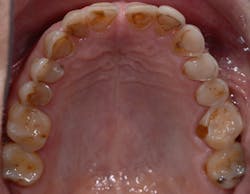

Figure 9: In an occlusal view of Patient A, the extreme wear and erosion is now very visible on almost every tooth—a powerful image for patients who can’t see this themselves.